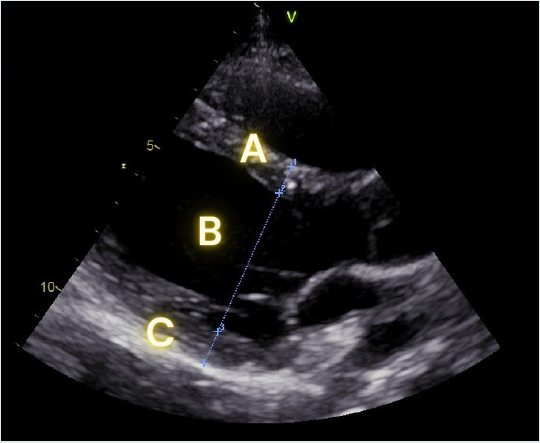

Parasternal long axis measurements

Measure these parameters in diastole (when the LV is the biggest):

A: Intraventricular septum thickness

B: End diastolic LV diameter

C: Posterior wall thickness